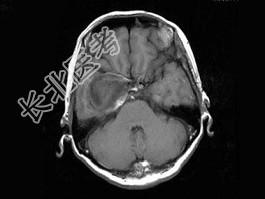

- 单项选择题女,62岁, 头痛数年,头颅MRI检查如图, 最可能的诊断是 ( )

A、脑膜瘤

B、动脉瘤

C、脑出血

D、转移瘤

E、未见异常